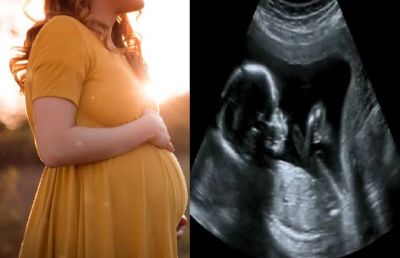

गर्भवती के साथ अल्ट्रासोनोग्राफी कक्ष के अंदर नहीं जा सकेंगे अटेंडेंट

Karnataka में अवैध गर्भपात पर कड़ी कार्रवाई के बावजूद, कन्या feticide बेरोकटोक जारी है। अवैध लिंग परीक्षण पर शिकंजा कसते हुए स्वास्थ्य विभाग ने अब ultrasonography room के अंदर गर्भवती महिला के साथ किसी भी अटेंडेंट के प्रवेश पर रोक लगा दी है। इसके अलावा, अल्ट्रासाउंड कक्ष में अतिरिक्त मॉनिटर के प्रदर्शन पर भी प्रतिबंध लगाया गया है।

PCPNDT Task Force के प्रमुख और स्वास्थ्य आयुक्त रणदीप डी. ने बताया कि निरीक्षण के दौरान स्कैनिंग केंद्रों पर कई उल्लंघन देखे गए हैं। परिपत्र का उद्देश्य गर्भधारण पूर्व और प्रसव पूर्व निदान तकनीक (पीसीपीएनडीटी) अधिनियम, 1994 को प्रभावी ढंग से लागू करना है। हाल ही में पीसीपीएनडीटी कार्यशाला में कई radiologist और स्त्री रोग विशेषज्ञों ने चिंता जताई कि थी कि गर्भवती महिला के साथ परिजन अल्ट्रासोनोग्राफी कक्ष में जाते हैं और अल्ट्रासाउंड प्रक्रिया का वीडियो बनाते हैं या तस्वीरें लेते हैं। उन्होंने यह भी चिंता व्यक्त की थी कि रिकॉर्ड किए गए video का उपयोग भ्रूण के लिंग की पहचान करने के लिए किया जाता है। यह धारा 5, उपधारा (2) के तहत पीसीपीएनडीटी अधिनियम का उल्लंघन है।

राज्य पीसीपीएनडीटी के नोडल अधिकारी विवेक दोराई ने कहा कि राज्य में एक नया चलन उभर रहा है, जिसमें भ्रूण का लिंग निर्धारित करने के उद्देश्य से अल्ट्रासाउंड प्रक्रिया के वीडियो बनाए जाते हैं। विदेश में रहने वाले अपने दोस्तों या रिश्तेदारों के साथ साझा कर लिंग निर्धारित करते हैं। उन्होंने कहा कि अल्ट्रासाउंड कक्ष में एक अतिरिक्त मॉनिटर होता है, जो गर्भवती महिलाओं को अल्ट्रासाउंड प्रक्रिया देखने में सक्षम बनाता है। कभी-कभी, रेडियोलॉजिस्ट, बिना कुछ कहे या कोई इशारा किए, लिंग का संकेत देने के लिए भ्रूण के निजी अंगों पर इशारा कर सकते हैं। इसलिए पीसीपीएनडीटी अधिनियम के प्रभावी क्रियान्वयन के लिए अल्ट्रासाउंड कक्ष में अतिरिक्त मॉनिटर का प्रदर्शन वर्जित है।